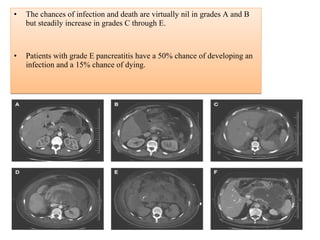

• The chances of infection and death are virtually nil in grades A and B

but steadily increase in grades C through E.

• Patients with grade E pancreatitis have a 50% chance of developing an

infection and a 15% chance of dying.

POINTSPOINTS

GradeGrade of Acute Pancreatitis

A = Normal pancreas 0

B = Pancreatic enlargement 1

C = Pancreatic/peripancreatic

inflammation 2

D = Single peripancreatic fluid collection 3

E = Multiple fluid collections 4

Grade E = 50% chance of developing an infection and 15% chance of deathGrade E = 50% chance of developing an infection and 15% chance of death